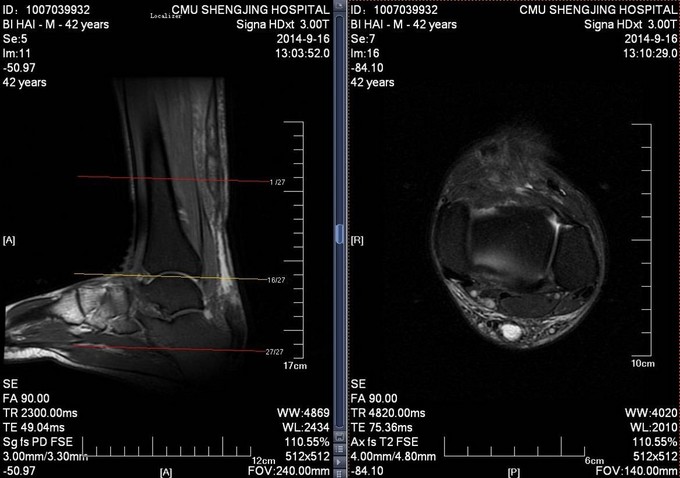

患者于2014年7月28日打排球时不慎摔伤,自觉左足跟部一过性剧烈疼痛,意识清醒。自觉足跟部及小腿后侧远端疼痛、行走时左足无力。于2014年9月10日就诊于当地医院,行相关查体后提示:左脚跟腱断裂。患者为进一步治疗门诊以“左跟腱断裂”为诊断收入病房

患者生命体征平稳,跟腱后方凹陷。局部可触及缺损,Thompson征阳性。

诊断:左陈旧性跟腱断裂 入院完善检查后,行左跟腱翻转修补术,术后踝关节跖屈石膏固定。